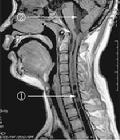

脊髓空洞症MRI檢查:空洞顯示為低信號,矢狀位出現於脊髓縱軸,橫切面可清楚顯示所在平面空洞的大小及形態。MRI對本病診斷價值較高。